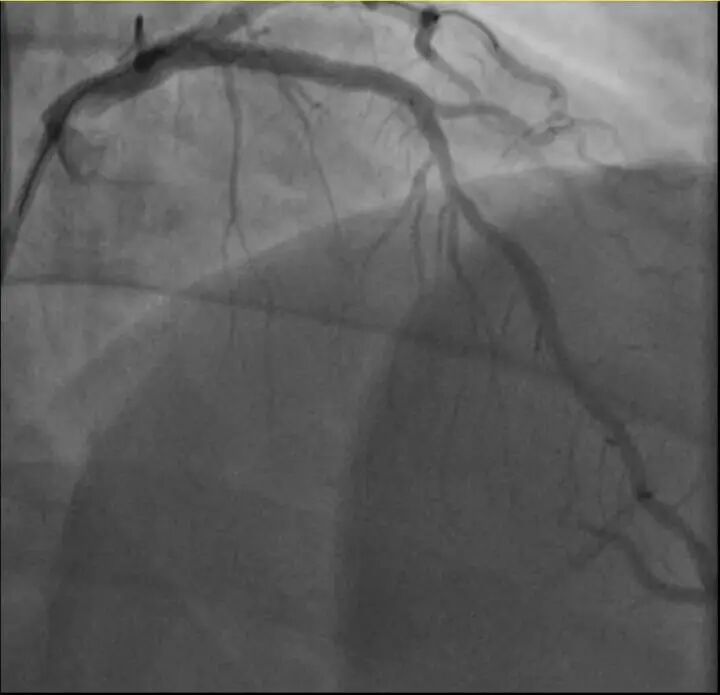

介入治疗后影像图

同一天

38岁的钱先生(化名)

也有类似遭遇

钱先生的血糖一直偏高,服药后控制不佳,但年轻的他并没有太上心。周末,他和孩子爬了一座山,隔天就因突发胸骨中段压榨性疼痛被送到了急诊,最后被证实也是心梗——心脏三支主要血管之一回旋支远段次全闭塞。

医生介绍,钱先生来院时血糖12.79mmol/L(正常空腹值应该在3.9~6.1mmol/L),甘油三酯也超标。三高是导致动脉粥样硬化(包括心脏的冠状动脉)的主要危险因素,在冠状动脉粥样硬化早期,血管狭窄可能并不严重,仅当血管狭窄到一定程度时,在运动、情绪激动等情况下,心肌耗氧量增加,就可能造成心梗等急性心肌缺血事件。

所幸及时治疗,钱先生也转危为安。